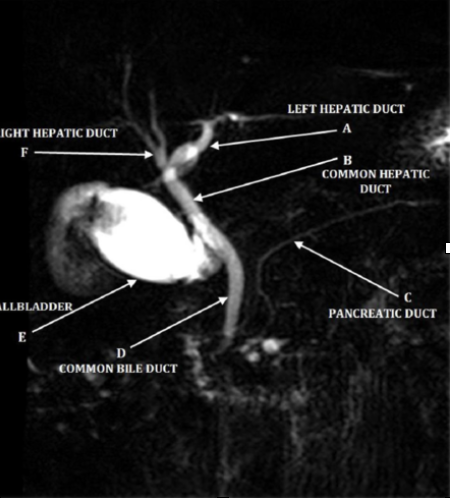

ERCP

-invasive, involves sedatives, radiation and more costly

-can cause pancreatitis, infection, bleeding

-diagnostic and therapeutic (stent, remove gallstones)

-gold standard for diagnosis of biliary obstruction

MRCP

-noninvasive, without anesthesia or radiation, cheaper

-improved visualization

-contraindicated with pacemakers and cochlear implant

-diagnostic but NOT therapeutic (delays treatment)